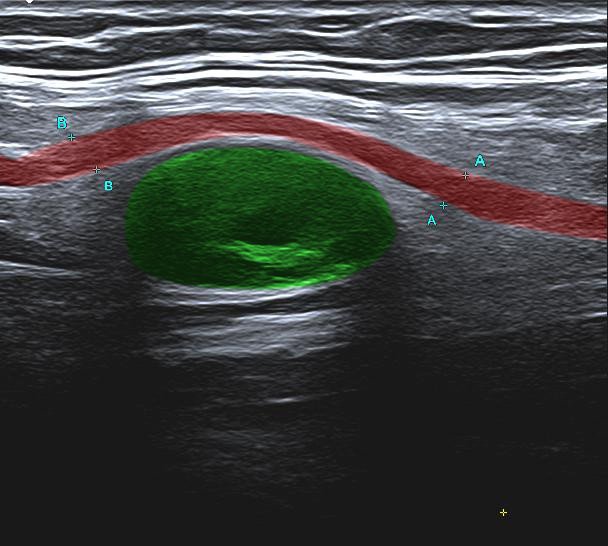

Nervenultraschall (Sono radialis)

Nervenultraschall des Nervus radialis am Oberarm: das rot eingefärbte Band zeigt den Verlauf des Nerven (N. radialis) und die ovale grüne Struktur ein Hämatom (Blutung), das den Nerv auf die Seite drängt. Der Patient hat neurologische Symptome im Arm, die durch diesen Nervendruck bedingt sind.